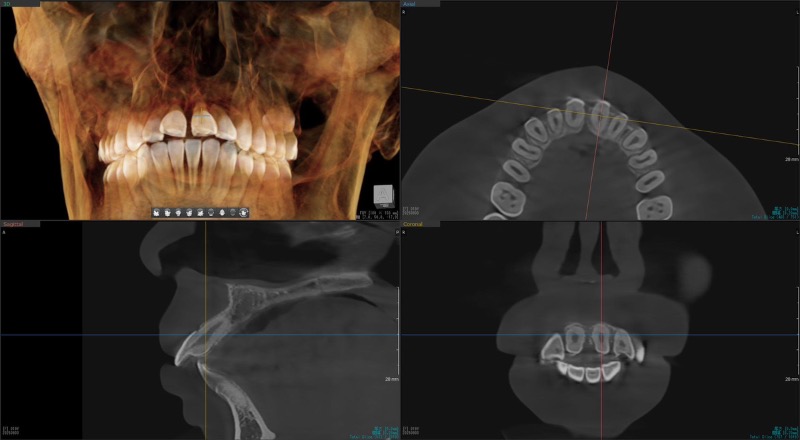

Q

Sさんのスマーティーチェックの確認お願いします

上顎の1番がソフト上では4mmの舌側移動

し、ソフト上の歯槽骨からは、はみ出て無いのですが、CT上では、???となっております。

どちらを信用すれば良いですか? -